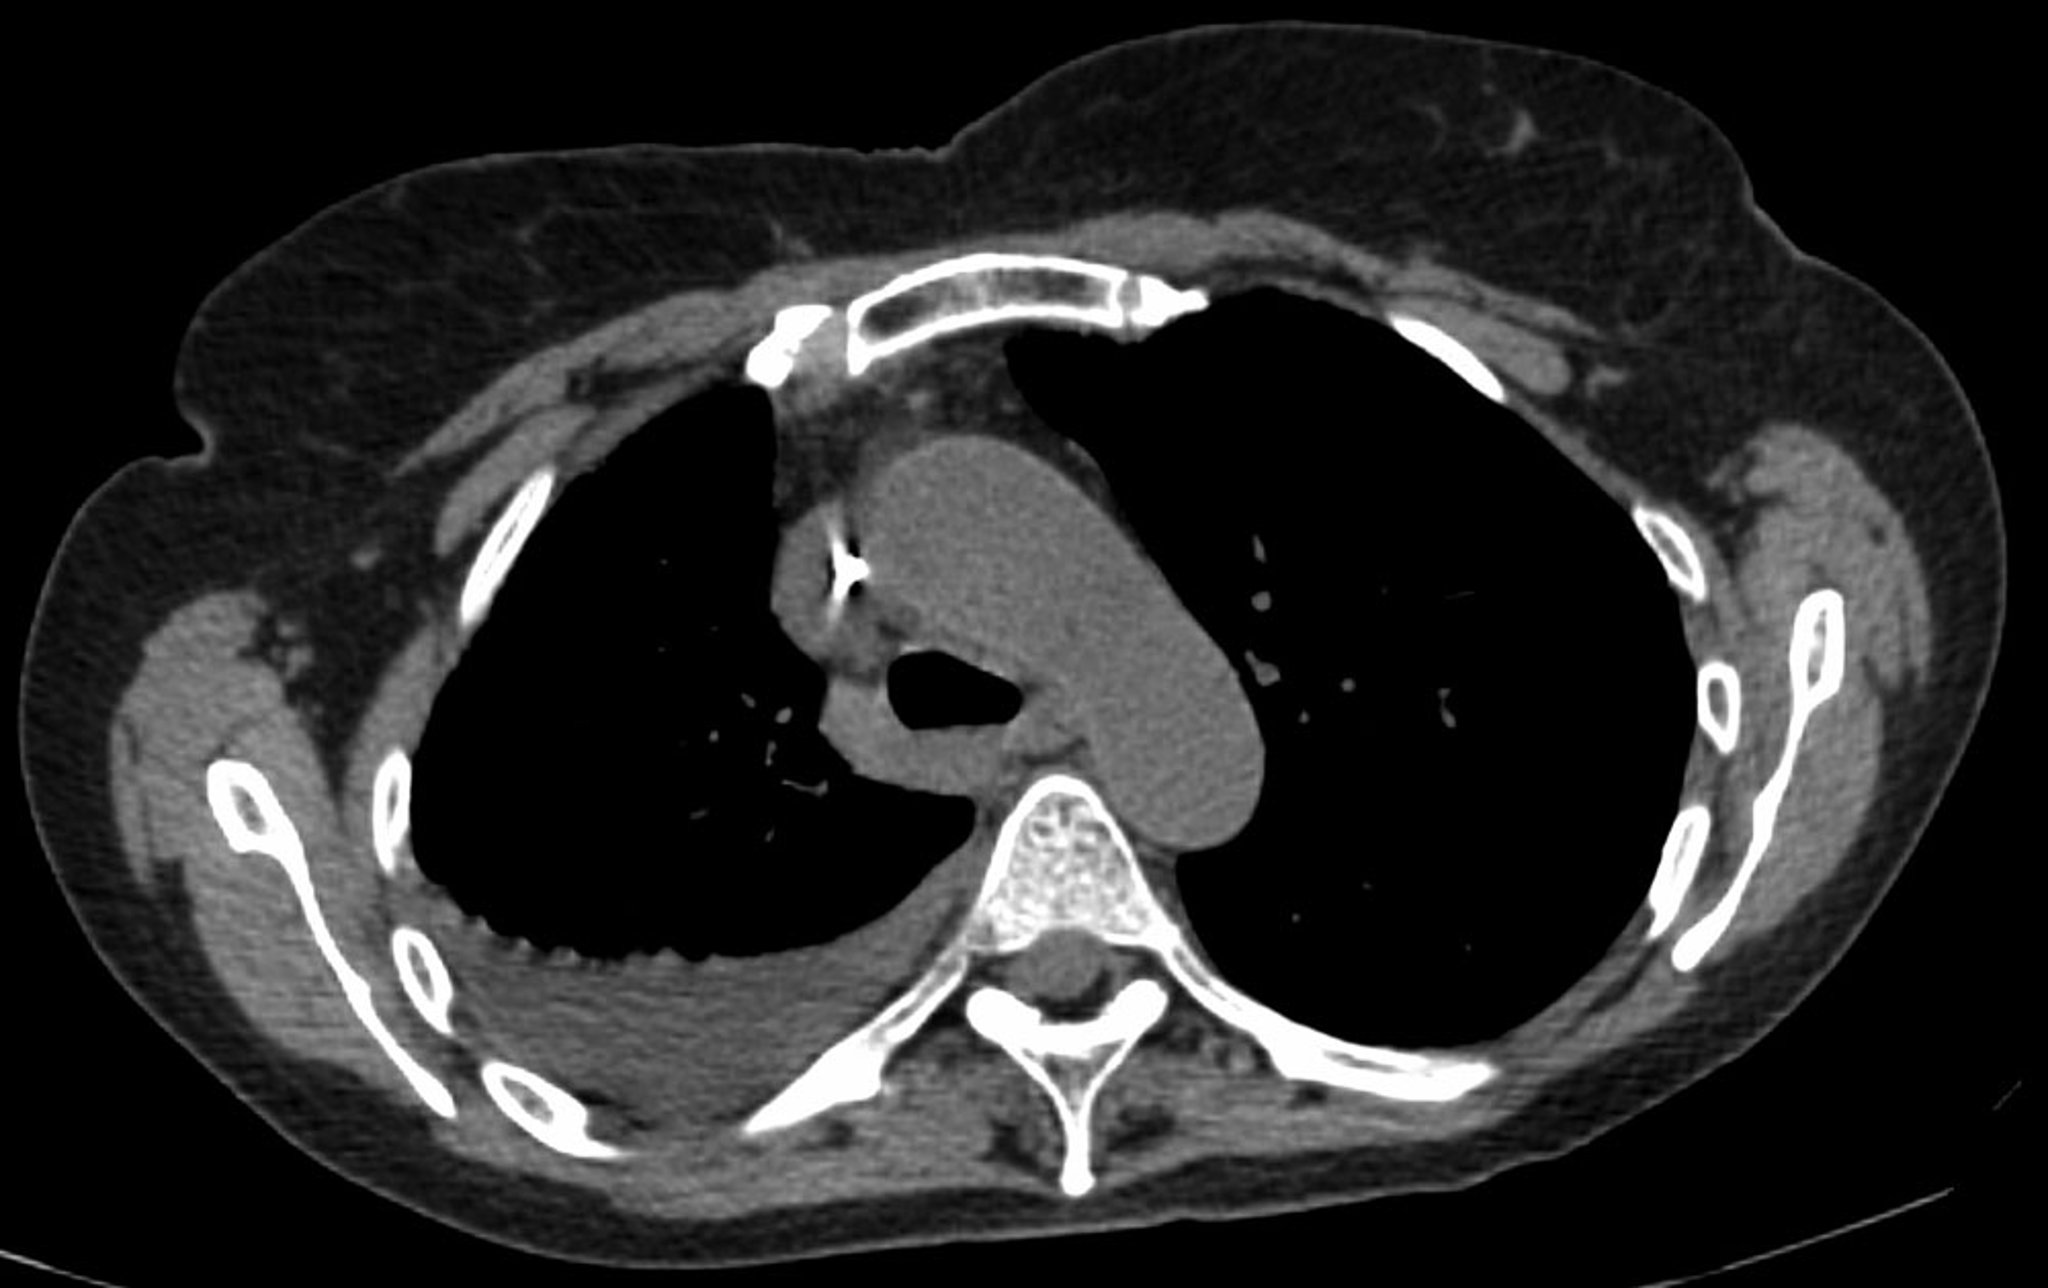

Right Pleural Effusion (CT Scan)

This image of an axial noncontrast enhanced CT scan of the chest reveals a small- to moderate-sized right pleural effusion in a female patient with breast cancer. (Mediastinal CT scan windows)